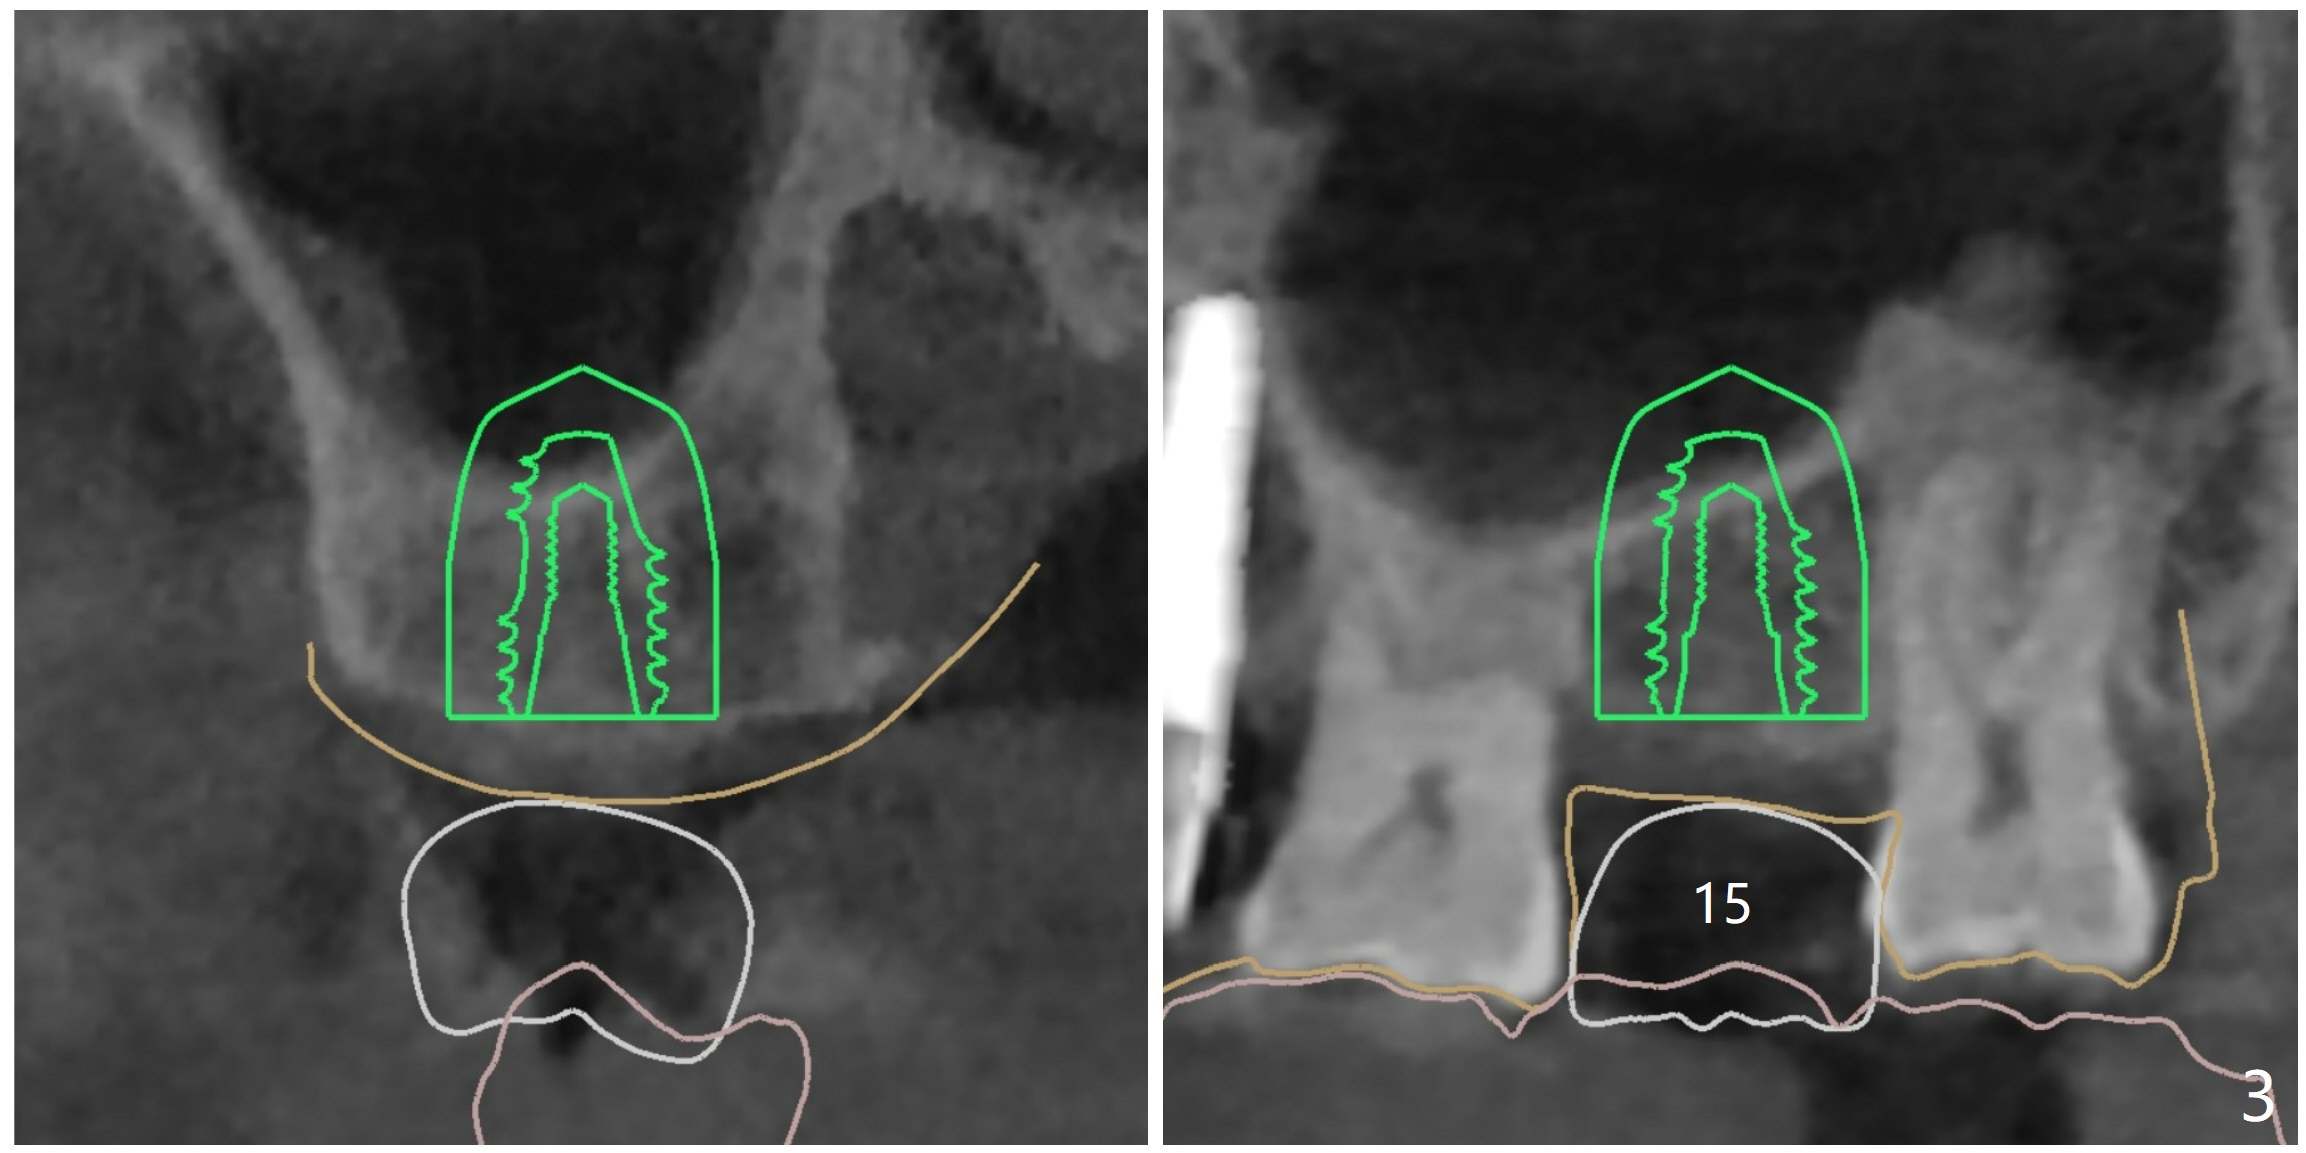

2号牙位点保存后6个月,而15号牙拔除没有植骨1-2年前(图一)。2号牙位骨质高度足够,准备不做上颌窦提升(图二),而15号牙位需要提升(图三,六)。种植术后5个月两个植体愈合均正常(图十一,十二)。